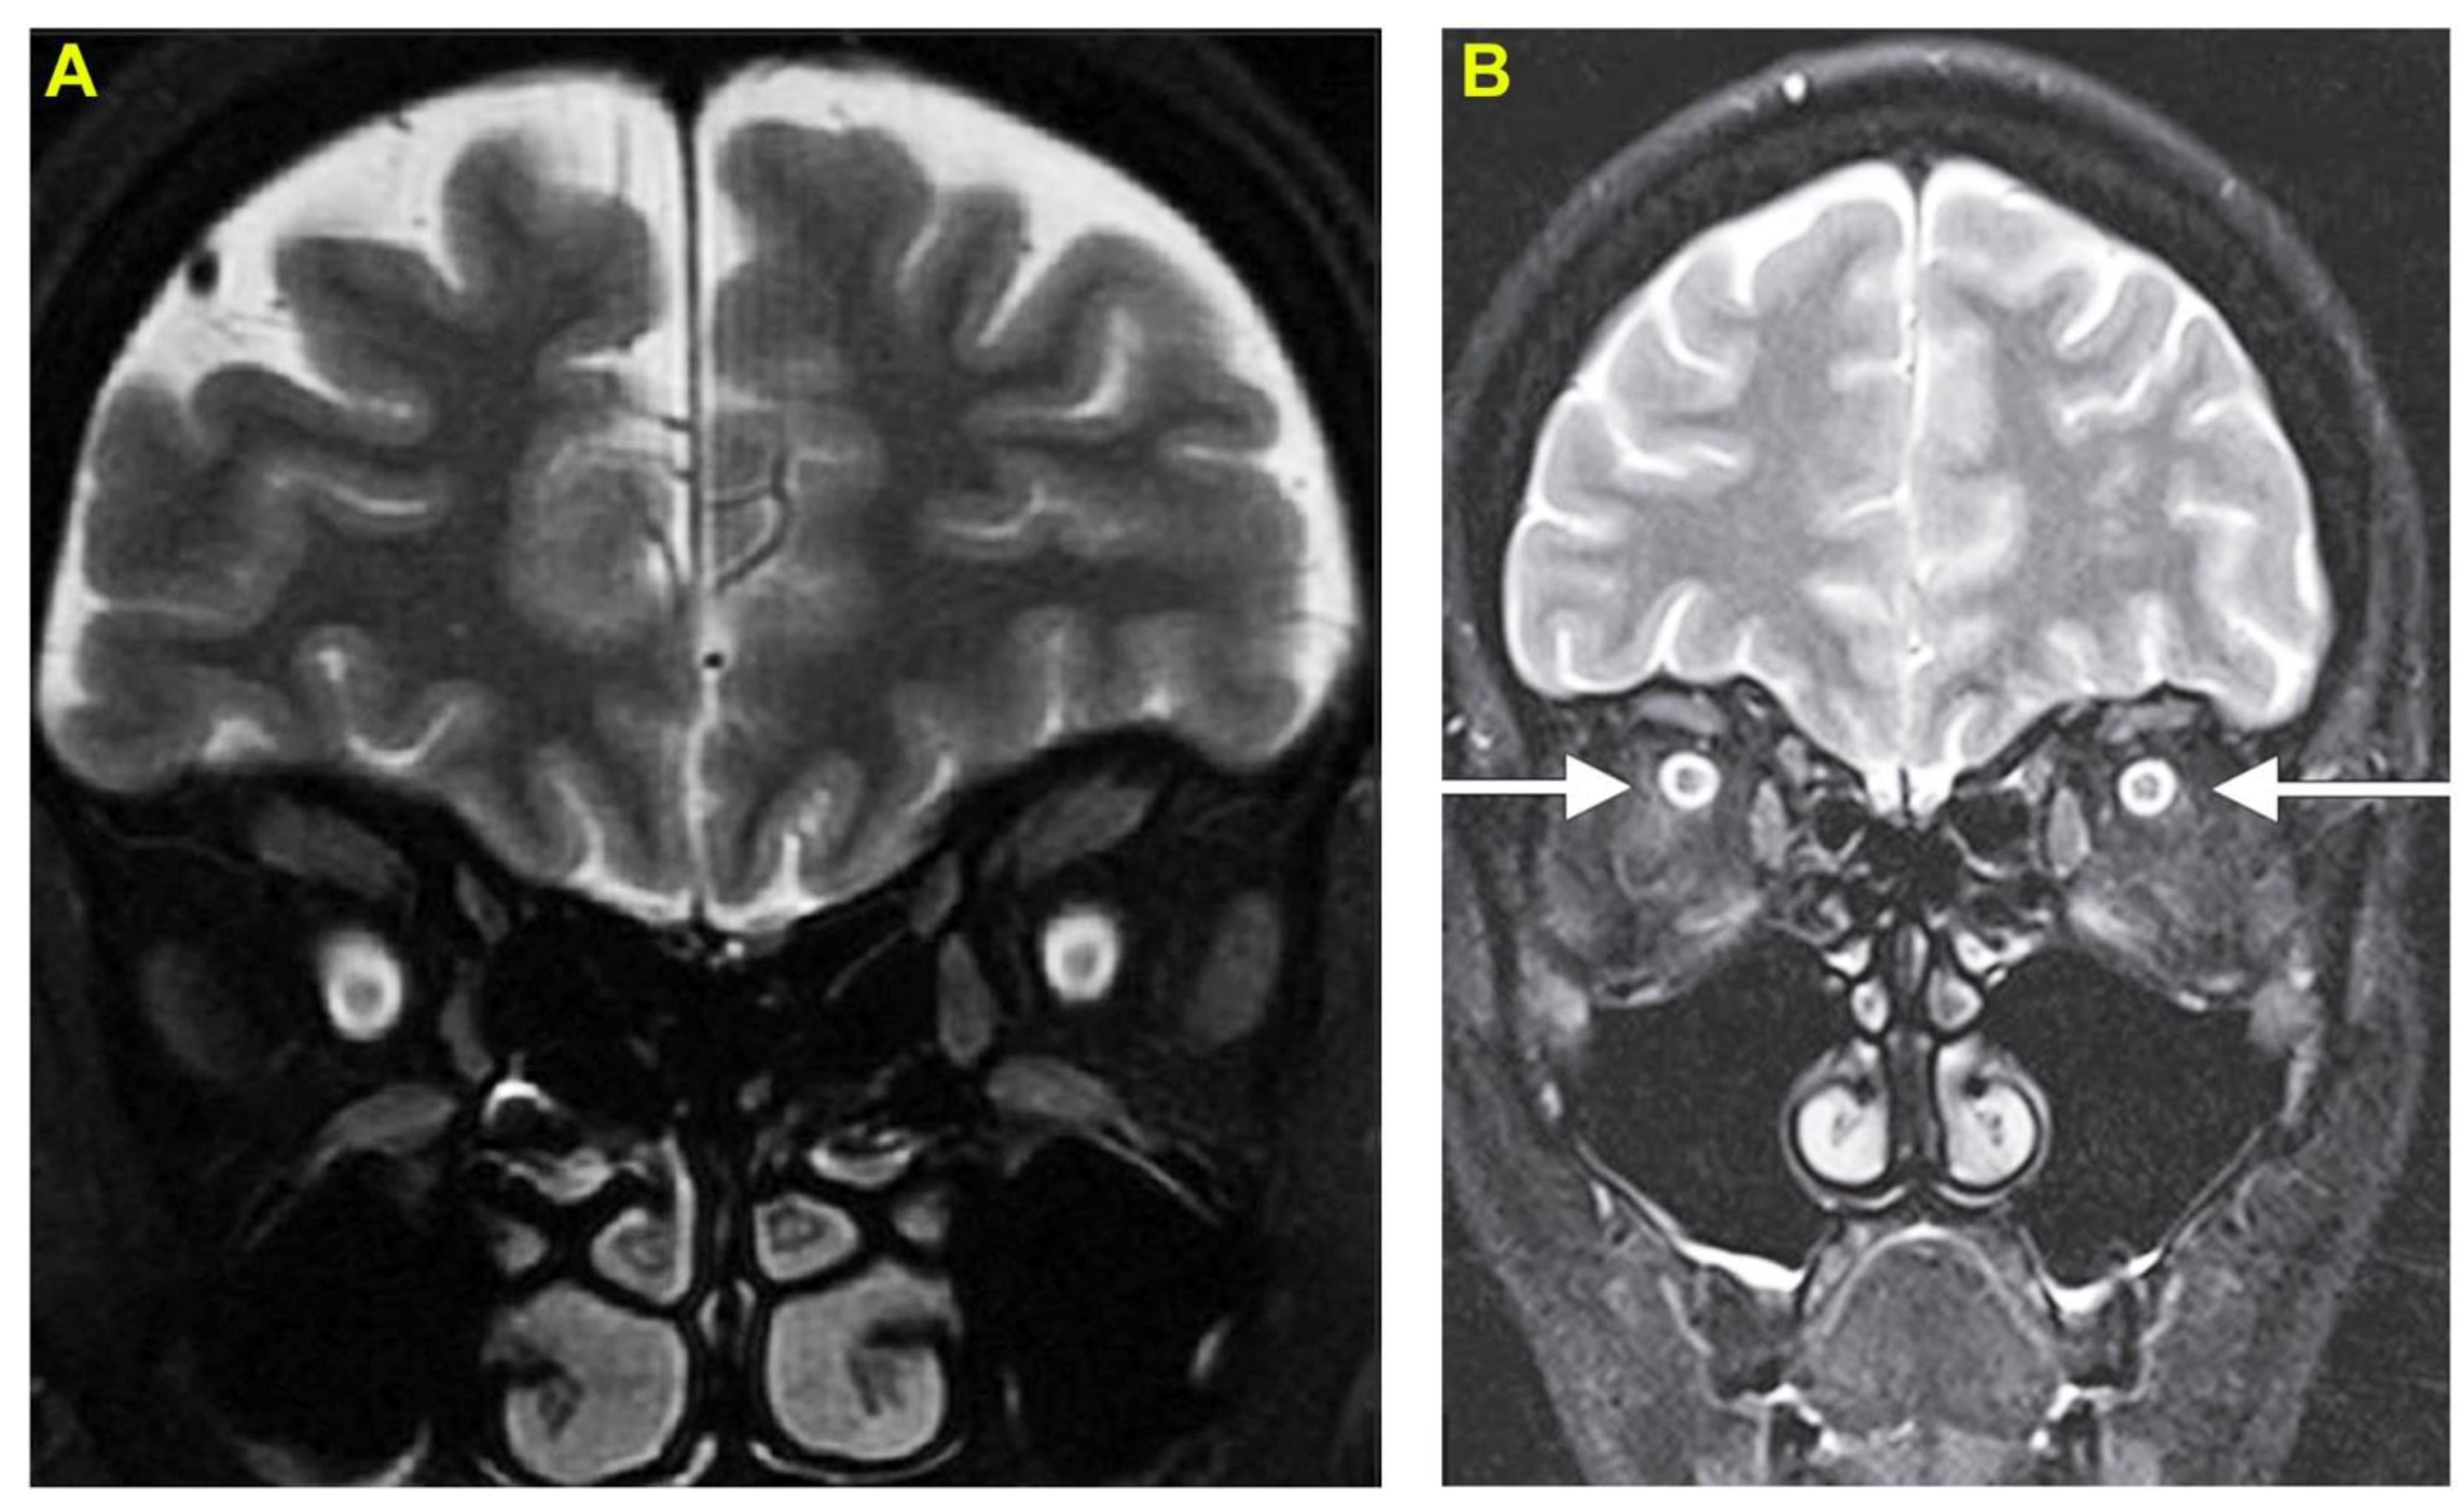

2. Case Report 1: Indian Cobra-Induced Optic Neuritis

3. Case Report 2: Common Krait-Induced Optic Neuritis